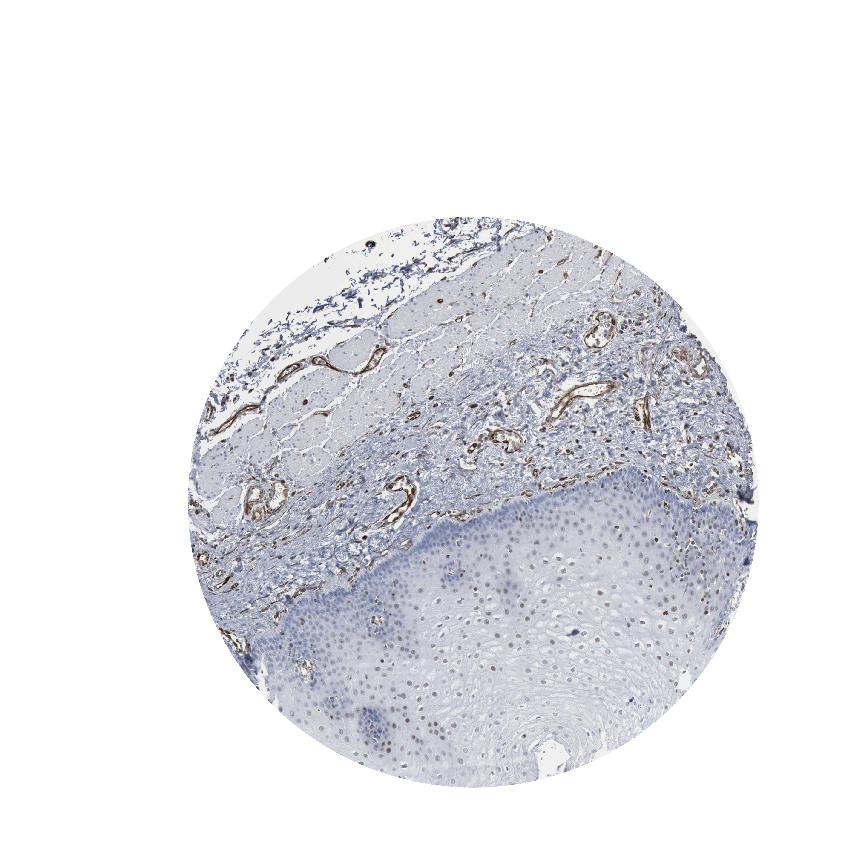

ESOPHAGUS - Antibody stainingi

Antibody staining in the annotated cell types in the current human tissue is reported as not detected, low, medium, or high, based on conventional immunohistochemistry profiling in selected tissues. This score is based on the combination of the staining intensity and fraction of stained cells.

Each image is clickable and will lead to virtual microscopy that enables deeper exploration of all samples and also displays staining intensity scores, fraction scores and subcellular localization as well as patient and tissue information for each sample.

Antibody HPA018169Antibody CAB000308Antibody CAB016682

Squamous epithelial cells MediumNot detectedLow